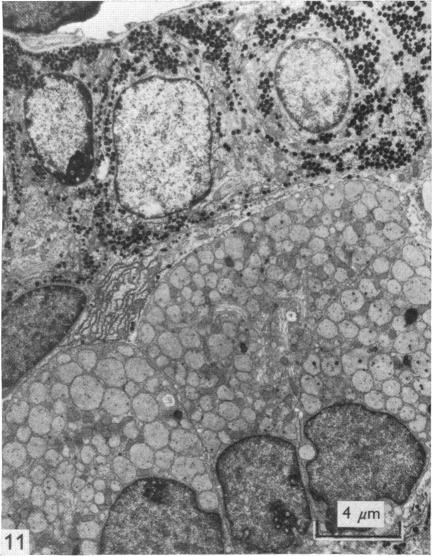

正常及经实验处理的田鼠(Microtus agrestis)垂体前叶的超微结构。

The ultrastructure of the anterior pituitary gland of the vole, Microtus agrestis, in normal and experimentally manipulated animals.

The ultrastructural appearance of the various types of cell present in the anterior pituitary of the vole has been described. There was a great measure of similarity between the cytological picture in this species and in the rat. Prolactotrophs contained the largest secretory granules, which were of variable shape; the granules of somatotrophs, whilst only slightly smaller than those of prolactotrophs, were invariably round, and of more uniform size; corticotrophs were represented by cells which were extremely angular, and whose secretory granules, besides being smaller than those of somatotrophs, were arrayed around the periphery of the cell below the plasma membrane; gonadotrophs contained granules of a similar size to those found in cortiocotrophs, but were found throughout the cytoplasm of the cells, whic were round to ovoid in shape; thyrotrophs contained the smallest granules of all, the shape of the cell itself bein angular...

已描述了田鼠垂体前叶中存在的各种类型细胞的超微结构外观。该物种的细胞学图像与大鼠的细胞学图像有很大程度的相似性。催乳素细胞含有最大的分泌颗粒,其形状各异;生长激素细胞的颗粒虽然仅比催乳素细胞的颗粒略小,但总是圆形的,且大小更均匀;促肾上腺皮质激素细胞由极具角状的细胞代表,其分泌颗粒除了比生长激素细胞的颗粒小之外,还排列在细胞膜下方细胞的周边;促性腺激素细胞含有与促肾上腺皮质激素细胞中发现的颗粒大小相似的颗粒,但存在于整个细胞的细胞质中,细胞呈圆形至椭圆形;促甲状腺激素细胞含有所有细胞中最小的颗粒,细胞本身呈角状……